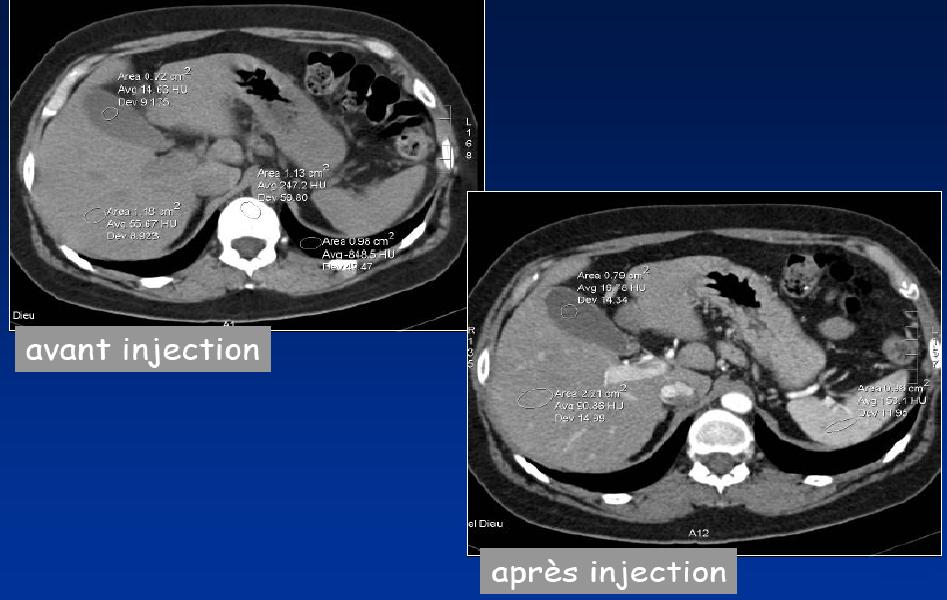

On distinguera différents temps : il y aura des temps sans injection, des temps précoces avec injection de 35 secondes (permettra de visualiser les vaisseaux (par exemple l'artere rénale ou l'aorte), des temps portaux ou parenchymateux (au niveau de la Veine Cave Inferieure) et des temps tardifs (permettront de visualiser des opacifications au niveau de la cavité rénale).

Le scanner va permettre de mesurer des densités (valeur avec un écart type), on observera ainsi des lésions hypo ou hyperdense.